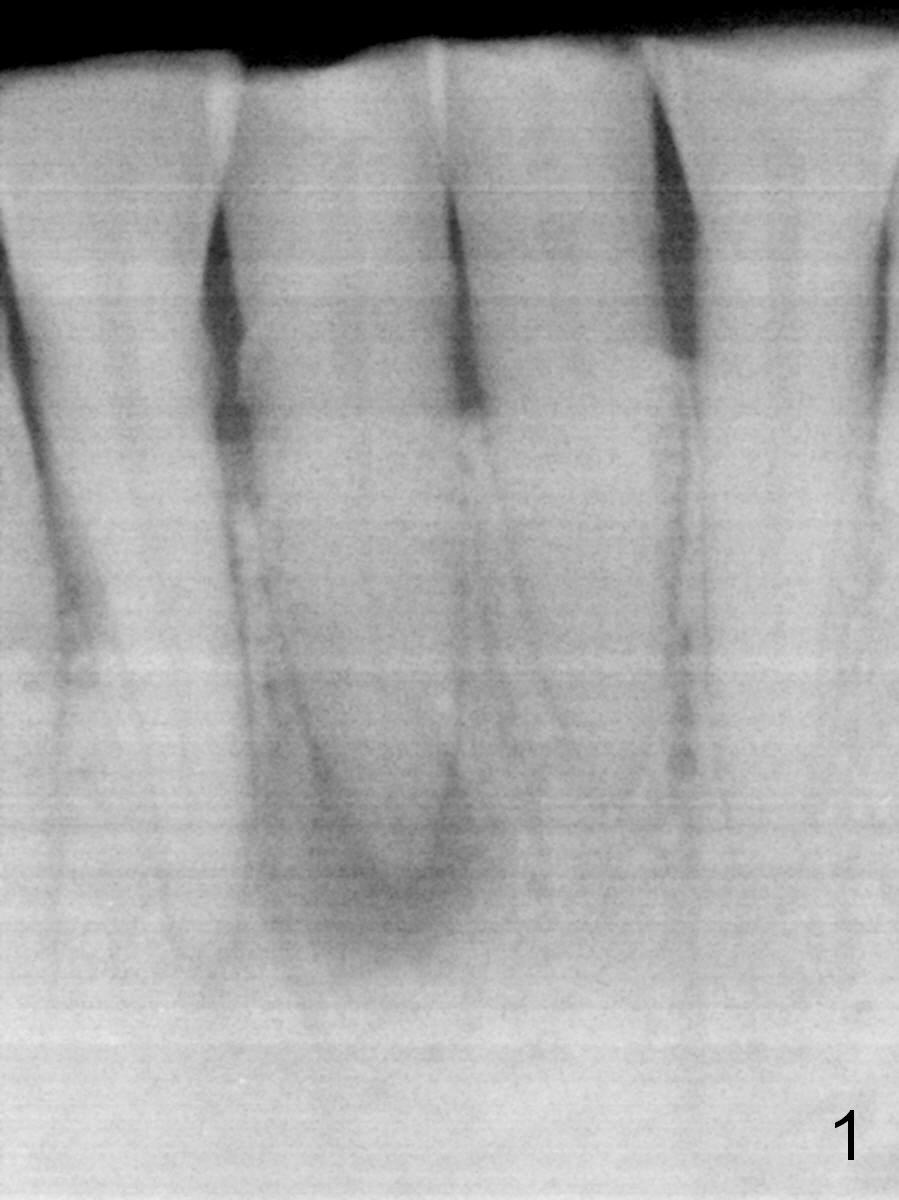

A 45-year-old man has had a chronic fistula associated with the tooth #25 (Fig.1). There is purulent discharge sometimes. How do you want to treat it?